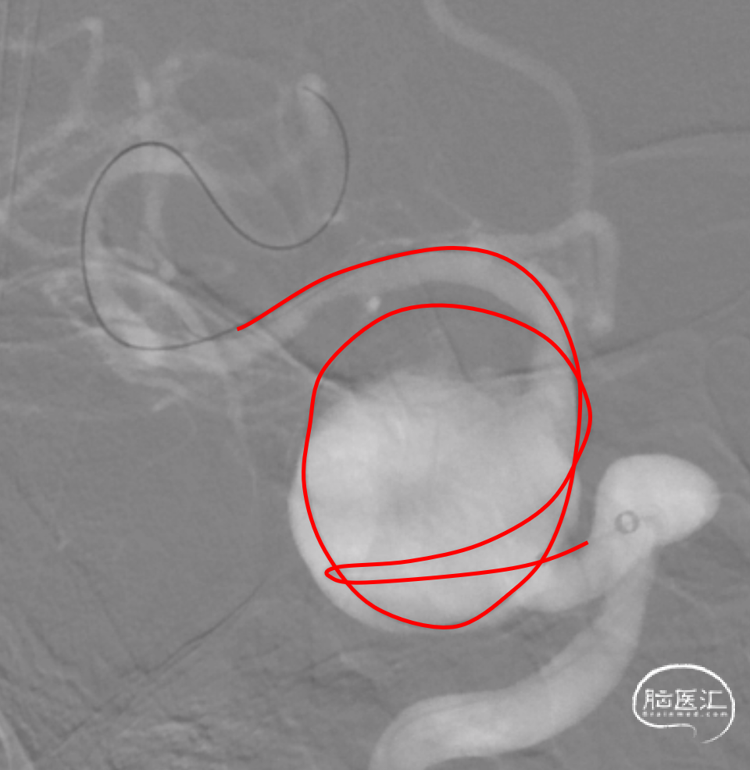

右侧颈内动脉海绵窦段多发大型动脉瘤

侧别、位置:

右侧颈内动脉海绵窦段

动脉瘤的形态:

球形、不规则

动脉瘤大小(mm):

长23.03mm、宽16.26mm

载瘤动脉直径(mm):

远端3.87mm、近端5.47mm

评估:

右侧海绵窦段大动脉瘤(23.03mm×16.26mm),动脉瘤血流动力学不稳定,海绵窦症状明显,患方治疗意愿强烈,手术指征明确;高龄,动脉瘤颈广泛扩张,密网支架为首选。

术后旋转,瘤内造影剂滞留,涡流消失。